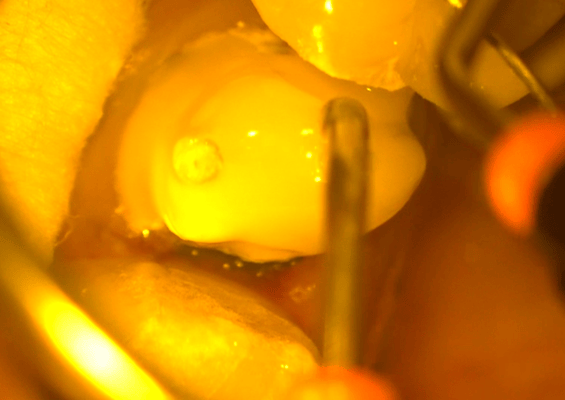

他院では抜歯と診断された歯ですが、それも間違えではありません。しかし、歯肉圧排をしたりすれば、保存できる可能性があることも多くあります。最初の状態ではラバーダム施すことが困難です。虫歯を除去中に歯髄の一部が露出しましたが、隔壁を作製し、防湿ができる環境を作って、歯髄を除去せずに保存できました。

クラウンを外すと、歯肉縁下までの大きな虫歯が確認できます。ラバーダムができないので、簡易防湿を行い、歯肉溝からの浸出液の侵入を防ぎます。隣の歯の間にまたがる虫歯ですが、丁寧に軟化象牙質を除去します。歯髄の露出はありましたが、特殊なセメントで緊密にシール(絆創膏みたいなもの)します。歯髄を除去せずにすみました。

ラバーダムを装着できるか否かは、治療結果を大きく左右します。